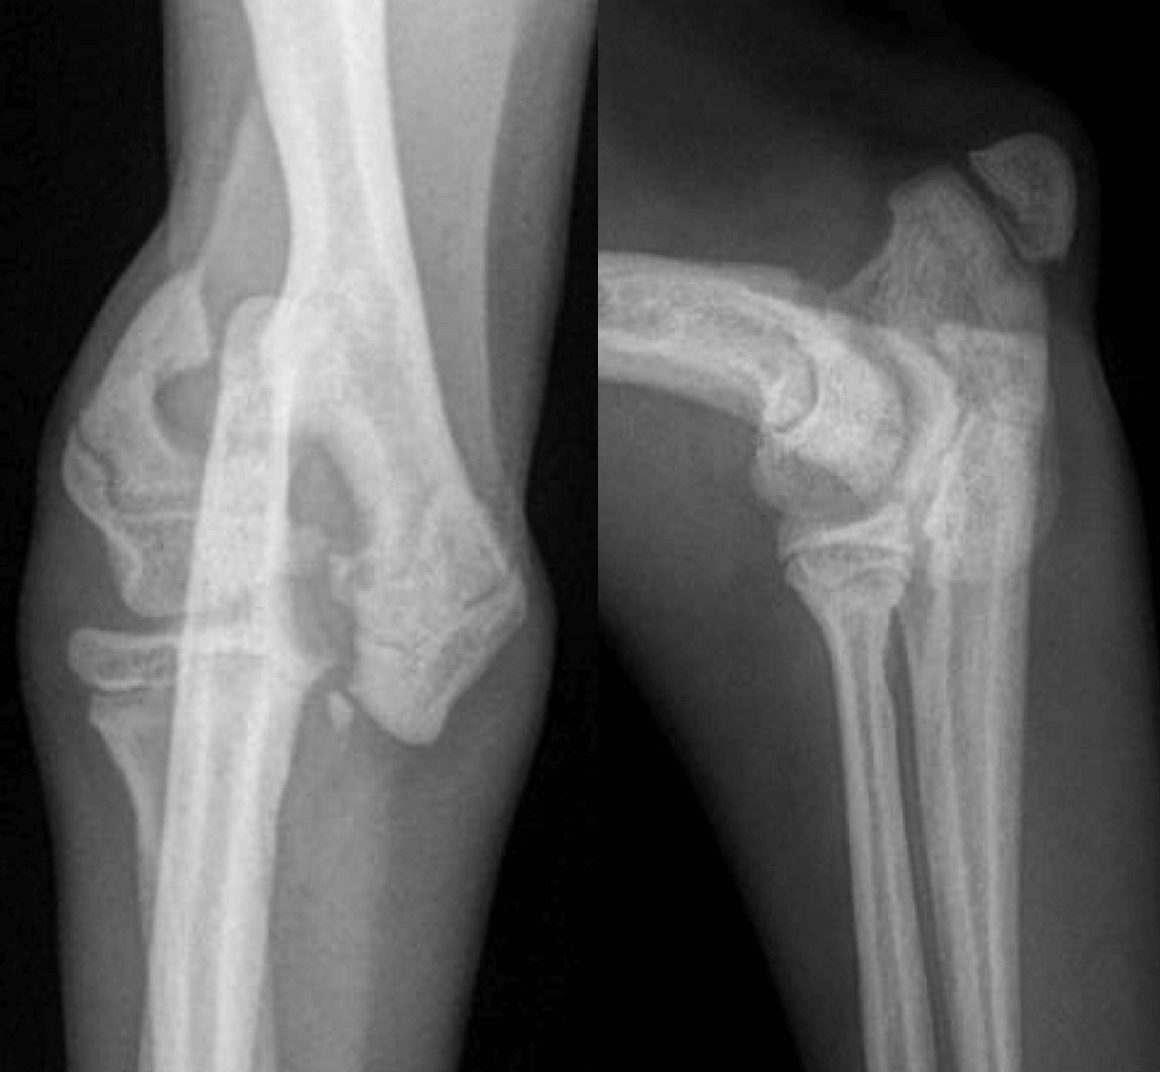

Salter Harris type IV de l’humerus distal sur Yuki un chihuahua de 3 mois (face et profil)